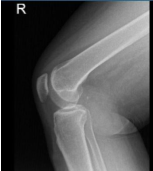

X-ray and MRI were presented in the office. Found vertical tear at the free edge margin of the posterior horn medial meniscus, with mild undersurface/free edge fraying of the body segment. Mild medial femorotibial compartment chondral loss. Mild patellofemoral compartment chondral wear, preferentially over the medial aspect of the compartment.

Lateral patellar tilt with mild lateral positioning of the patella. These findings may be seen in the setting of patellar malt racking. Features which may be seen in the setting of iliotibial band friction syndrome.

Lateral View